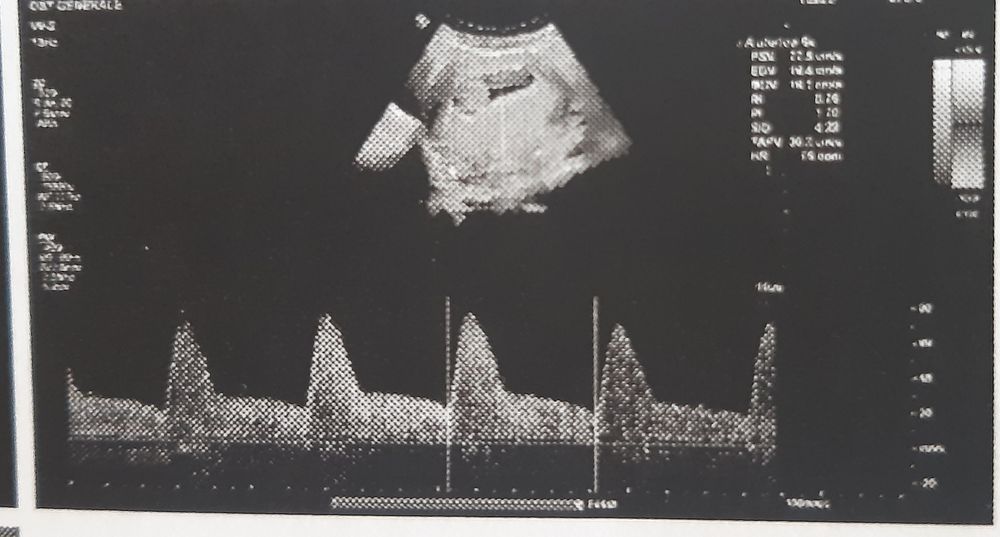

Не знаю, актуально ли, но увидела пост в дневнике и решила прочитать. ЧСС по английски - HR. Вижу на 1 фото HR 142 или 148, самая нижняя строчка. Остальные фото видимо артерии или что-то еще

Наталья, спасибо огромное! ❤🙏 Да, актуально очень! Это тот параметр, за которым мне нужно следить внимательно.